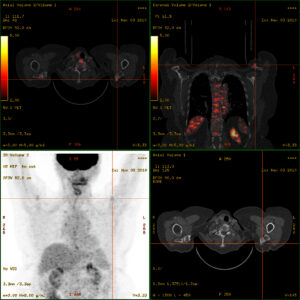

Tuttavia, per la stadiazione della maggior parte dei tumori solidi (es. mammella, polmone), la PET/TC con FDG è oggi spesso considerata la metodica di scelta in quanto fornisce una valutazione “tutto-in-uno” estremamente efficace. Non solo rileva le metastasi ossee con alta sensibilità, ma offre simultaneamente informazioni preziose sull’intero corpo, identificando metastasi in altri organi (fegato, polmoni) e linfonodi, cruciali per una stadiazione completa e per la pianificazione terapeutica.

Per il carcinoma della prostata, il vero gold standard sta diventando la PET con ligandi PSMA, altamente specifica per le cellule tumorali prostatiche.